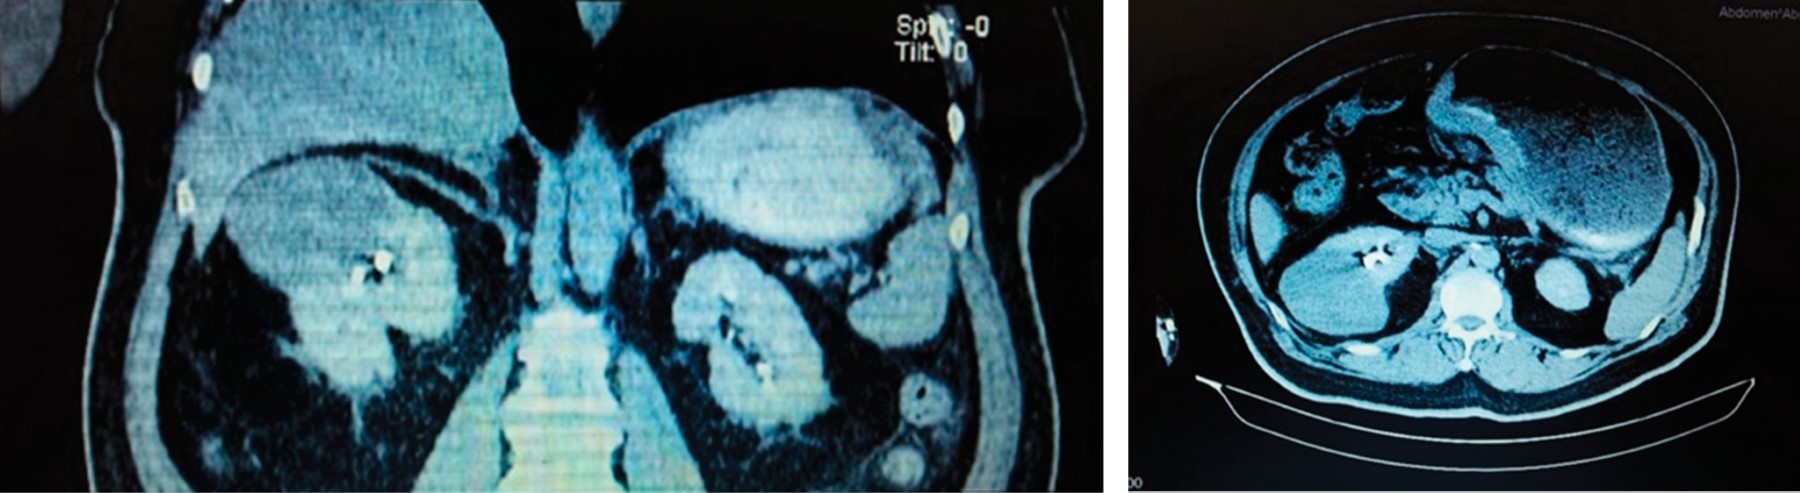

A 68 year-old male patient with history of diabetes mellitus, smoking, and chronic alcoholism for more than 20 years. He denied surgical history. The patient presented with intermittent abdominal distension, dyspepsia, progressive dysphagia from solids to liquids. He denied weight loss or data of gastrointestinal tract bleeding. A CT scan with intravenous contrast reported a right renal tumor of 7 × 6 × 4 cm with rounded edges, well defined, and a heterogeneous hypodense center related to cystic or necrotic degeneration (Figure 1). After intravenous contrast, a "claw sign" was present, with enhancement at 20 HU and a delayed triphasic phase enhancement of 10 HU. Also, a distended stomach with thickening of the antral and pyloric mucosa of 1.7 cm was found, with no hepatic or distant metastases. Panendoscopy showed infiltrating gastric neoplasia (Borrmann II adenocarcinoma) (Figure 2). The histopathological result of the gastric biopsy reported a poorly differentiated diffuse infiltrating adenocarcinoma with signet ring cells. The CA 19-9 marker value was 126 U/ml.

Figure 1